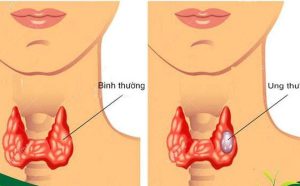

Ung thư là một bệnh lý liên quan đến sự tăng sinh không kiểm soát của tế bào trong cơ thể. Tế bào là đơn vị cơ bản của tất cả các mô và cơ quan trong cơ thể. Trong quá trình sinh tồn, các tế bào sẽ phân chia và thay thế những tế bào đã chết hoặc bị hư hỏng. Tuy nhiên, trong một số trường hợp, các tế bào này bắt đầu phân chia không kiểm soát và không chết đi như các tế bào bình thường, dẫn đến hình thành các khối u ác tính, gọi là ung thư.

Các khối u ác tính có thể lan sang các bộ phận khác trong cơ thể thông qua máu hoặc mạch lymph và gây tổn thương cho các tế bào và cơ quan khác. Nếu không được phát hiện và điều trị kịp thời, ung thư có thể dẫn đến nhiều biến chứng nguy hiểm và gây tử vong.

7 loại ung thư có khả năng chữa khỏi nếu phát hiện sớm

Như vừa được nêu trên, đã có nhiều loại bệnh ung thư có thể được chữa khỏi hoàn toàn hoặc được kiểm soát bàng các phương pháp điều trị khác nhau. Điển hình là 7 loại ung thư có khả năng chữa khỏi sau nếu phát hiện sớm và điều trị đúng phương pháp: